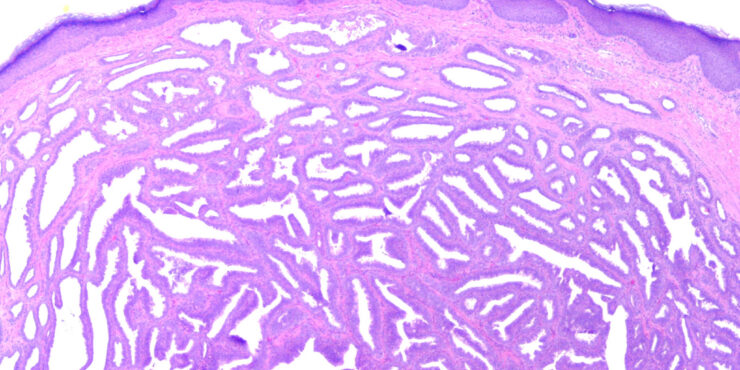

Read MoreNipple duct adenoma = غدووم في قناة الحلمة OLYMPUS DIGITAL CAMERA OLYMPUS DIGITAL CAMERA OLYMPUS DIGITAL CAMERA